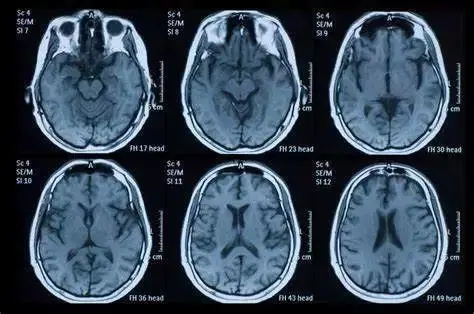

脑部MRI扫描图像